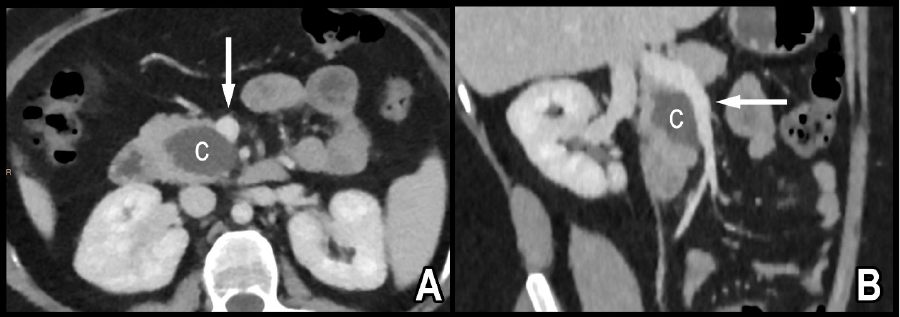

A 29-year-old female with a BMI of 34 kg/m2 presents with vague, persistent upper abdominal pain. Index cross-sectional computed tomography (CT) imaging shows a 3.6 × 3.1 × 4.0 cm hypodense pancreatic head lesion that was intimately associated with the right lateral border of the superior mesenteric vein (SMV) (Figure 1).

Figure 1. (A) Axial and (B) Oblique Contrast-Enhanced CT Images of Abdomen. Published With Permission

Water attenuation cystic lesion (c) in pancreas broadly contacts SMV (arrow).